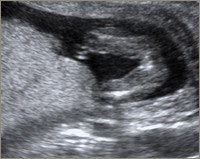

De første 3 billeder er alle uge 15. De to første er dreng og det sidste pige. Det sidste billede er også en pige... Kan derfor godt forstå at hun ikke er helt sikker på kønnet... men tror alligevel jeg tænker dreng

Vedhæftede fotos (klik for at se i fuld størrelse)

men synes vores ikke ligner dit "pige" billed

Jeg synes jeg kan se en sammenligning mellem dit nummer 2 billede og mit nummer 4 billede (som er en pige) og ellers så synes jeg at jeres ligner mest en dreng...